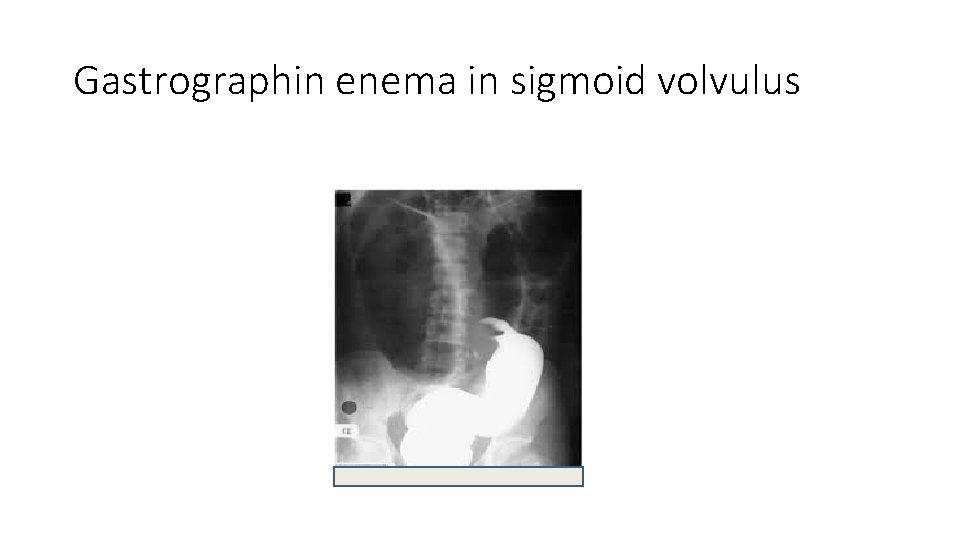

Contrast studies • include an enema with water-soluble contrast • Contrast studies that reveal a column of contrast ending in a "bird's beak" are suggestive of colonic volvulus.

Gastrographin enema in sigmoid volvulus